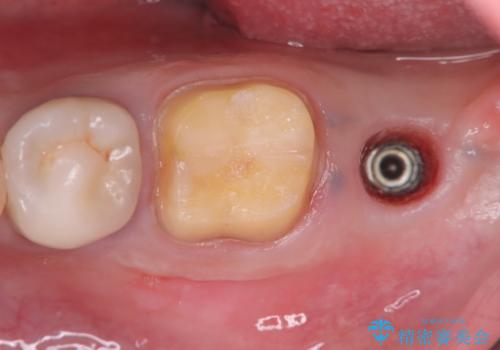

- 過去にヘミセクションが行われていたと思われる左下7番は、大きな歯根嚢胞および根尖病変が認められ、さらに骨縁下カリエスを伴っており、歯肉には瘻孔が形成されている状態でした。

保存は困難と判断し、左下7番は抜歯即時インプラントによる治療を行いました。

抜歯と同時にインプラントを埋入するため、歯茎を切開する必要がなく、術後の痛みが出にくい治療方法です。

手術は1回で完了し、被せ物を装着するまでの治療期間も約3か月と、身体的・時間的な負担を抑えることができます。